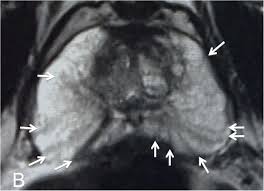

Https Epad Uroweb Org Wp Content Uploads 3 Role Of Mri J Barentsz Pdf

Https Epad Uroweb Org Wp Content Uploads 3 Role Of Mri J Barentsz Pdf from